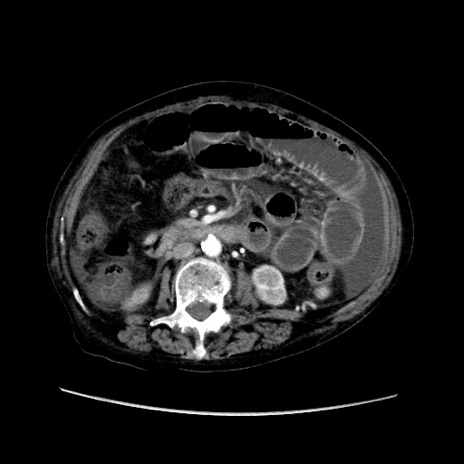

症例31(横断像)

【症例】80歳代 女性

【主訴】腹部膨満感

【現病歴】他院にて肝硬変にてフォロー中。1週間前から便秘、腹部膨満感、臍部腫瘤あり受診となる。

【既往歴】肝硬変

【身体所見】腹部膨隆あり、皮膚変化なし、疼痛なし。

【データ】WBC 4600、CRP 0.25